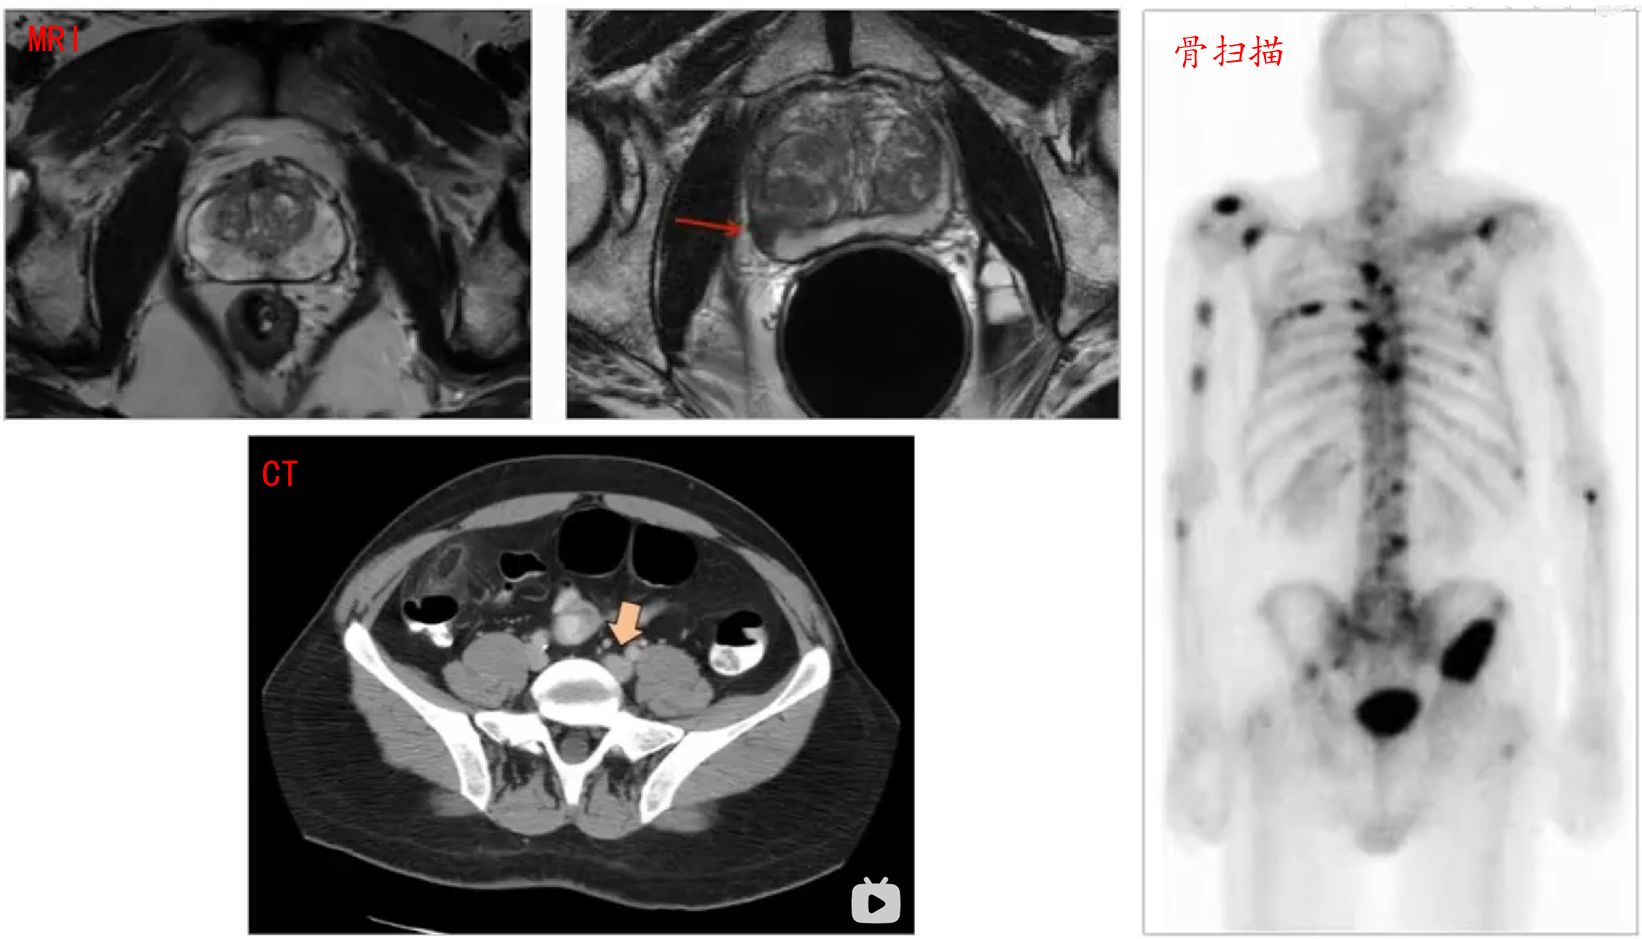

• 核磁共振(MRI):检查PC是否突破前列腺包膜,侵入其它周围组织

• CT扫描:观察淋巴结是否变大(可能是由于PC转移,也有可能是炎症等导致)

• 骨扫描/X-rays:观察是否存在骨损伤(可能是由于PC转移)

image-20240919195224798